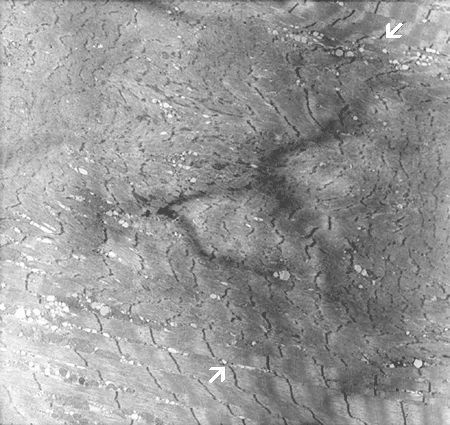

The myofibrils of the core (in between àÝ) are not in the same register with the surrounding myofibrils. The I-bands are reduced in length and the Z-disc is fussy.